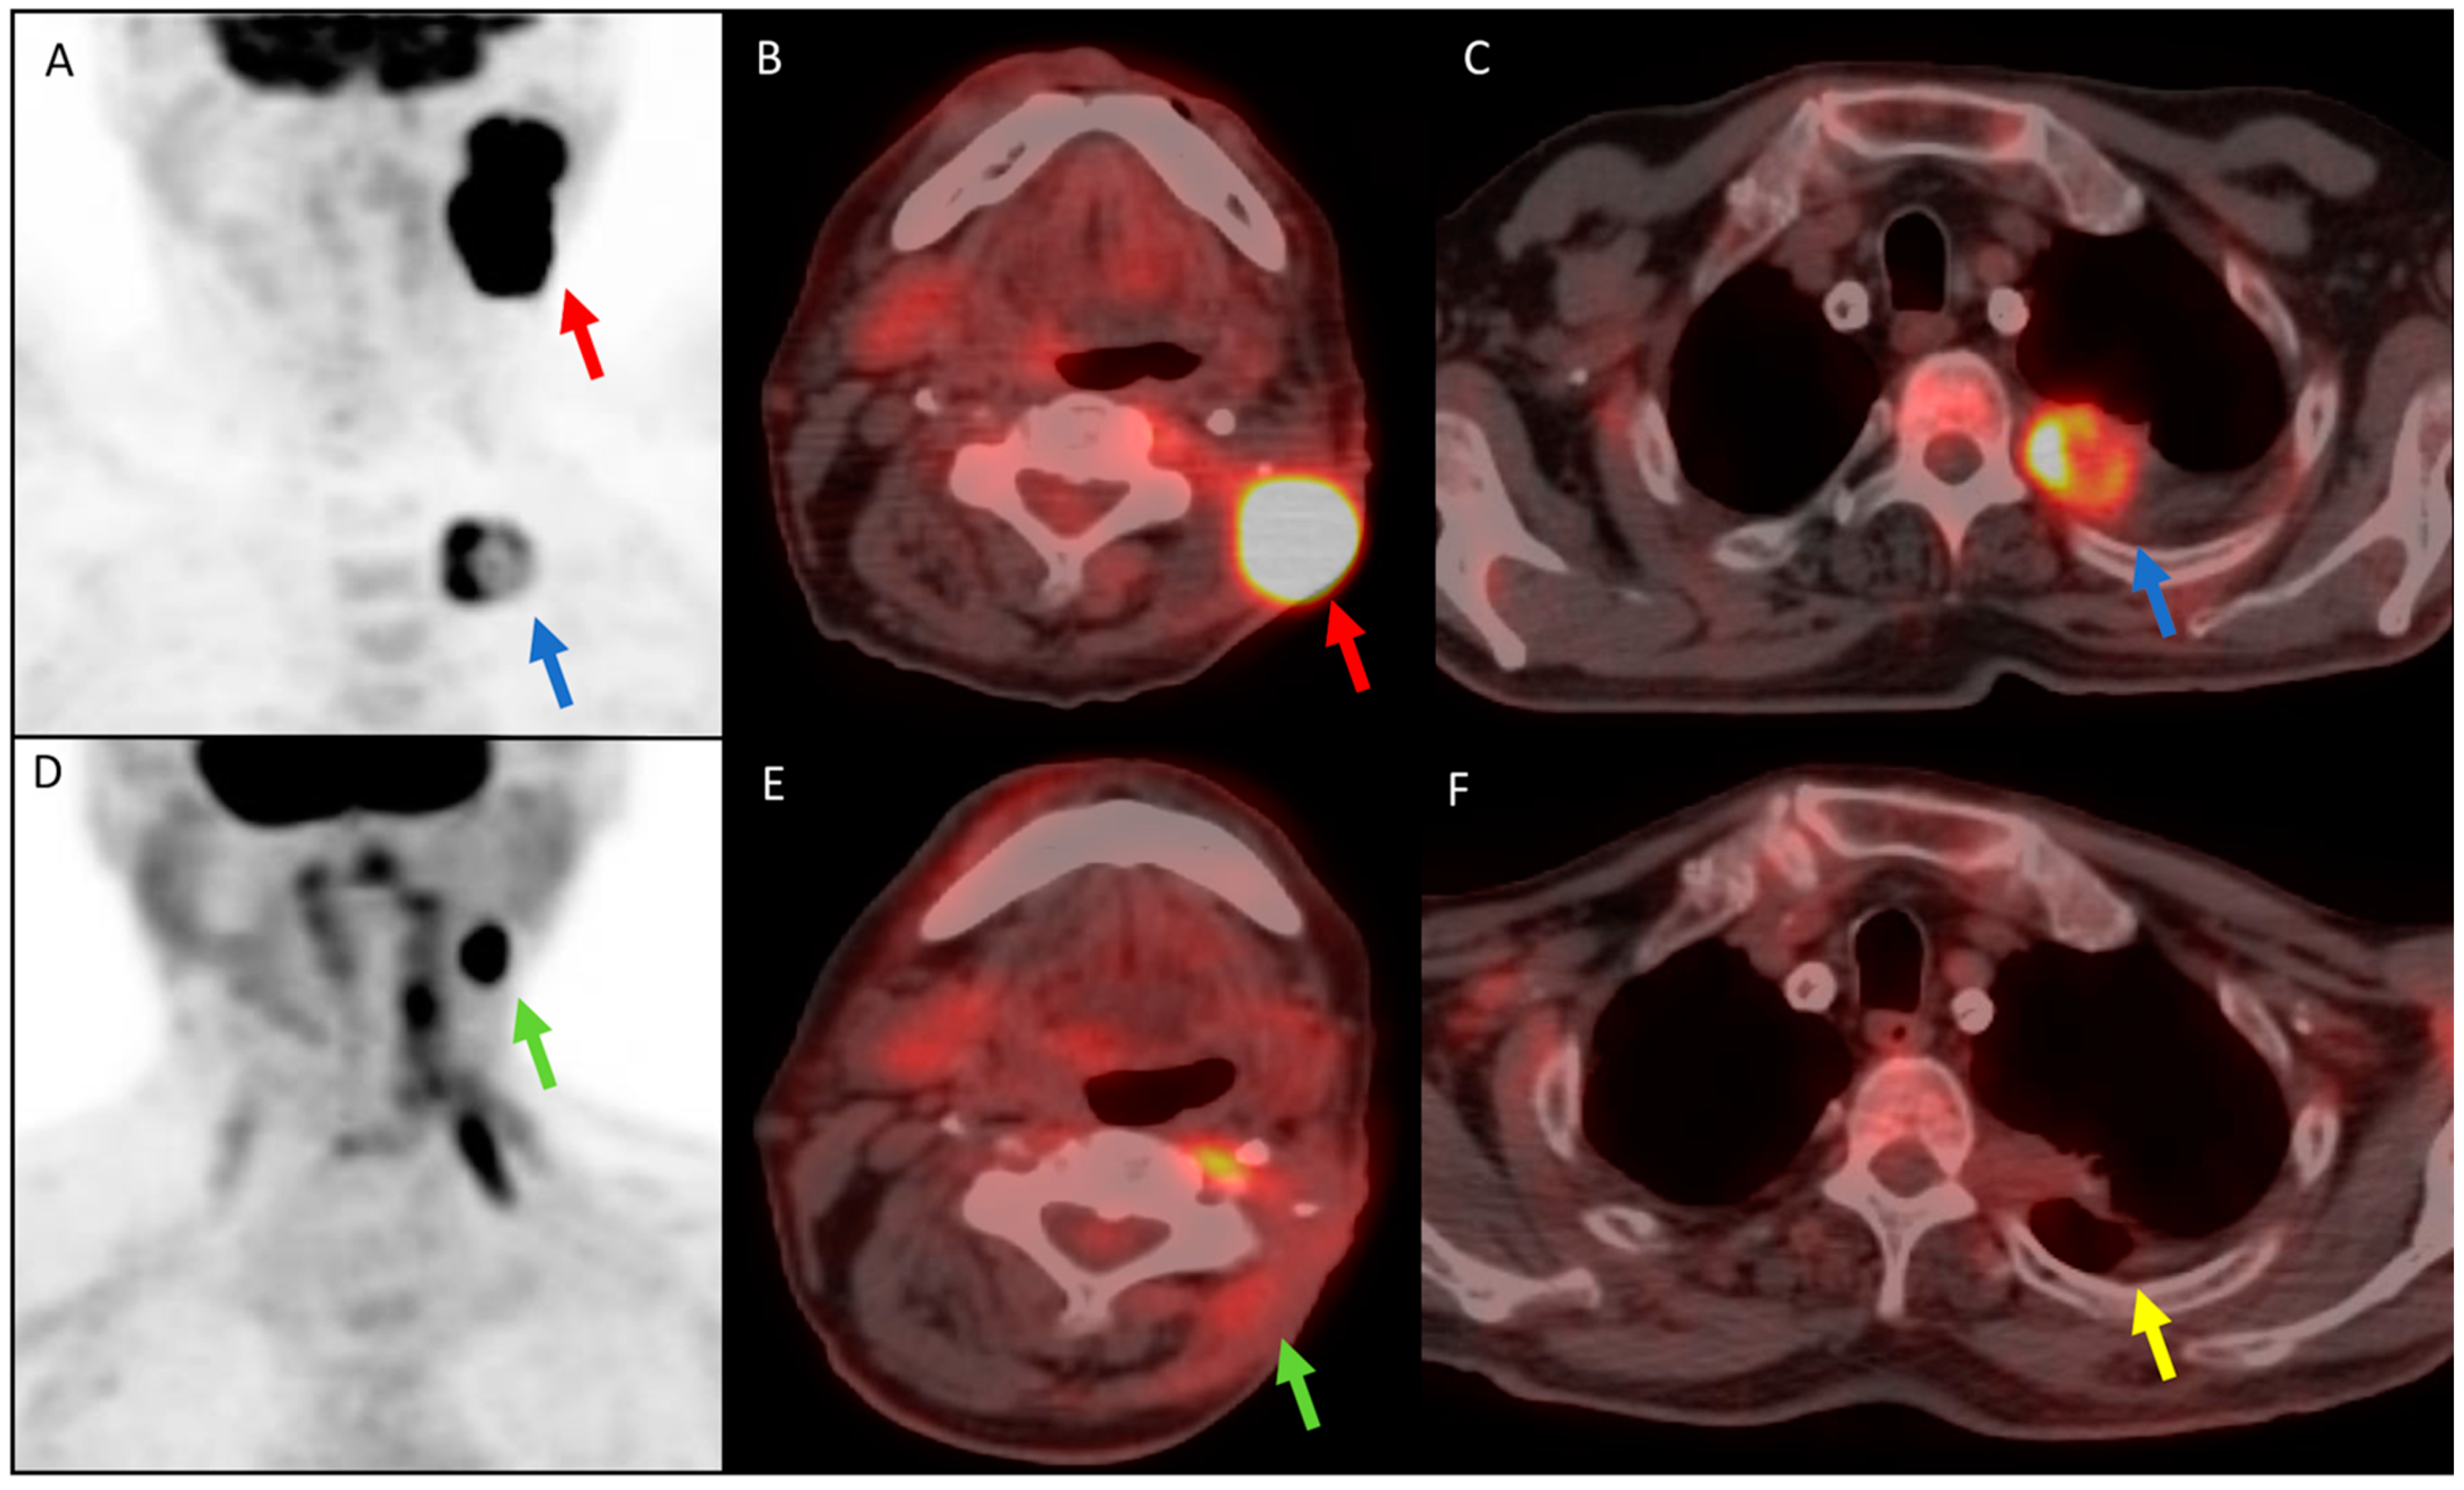

Heterogeneous Response to Immunotherapy in a Patient with Tonsillar Squamous Cell Carcinoma Assessed by 18F-FDG PET/CT